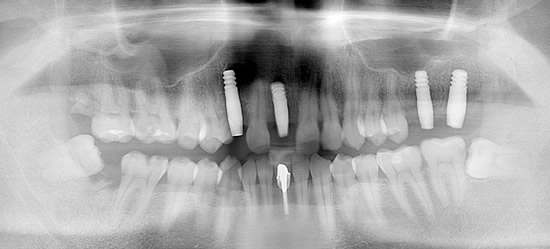

症例4

治療前

治療後

- 年齢・性別

- 60歳

- 治療期間

- 6ヶ月

- 抜歯

- 残根抜歯のみ

- 治療費

- 184.8万円

- 備考

- 右上5.6 右下5 左下4.5.6欠損

- 治療内容

- 6本のインプラントを右左側に2回に分けて埋入

- 施術の副作用(リスク)

- オペによる知覚障害。インプラントによる歯肉炎。インプラント脱落。